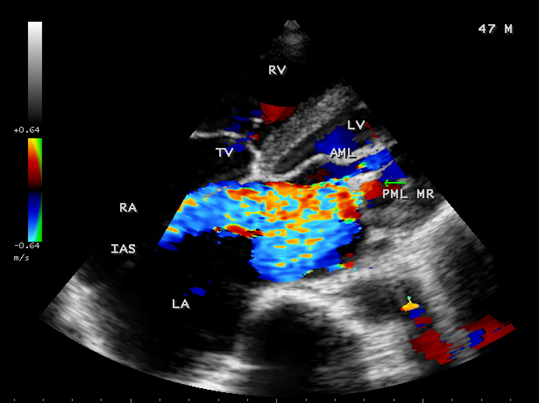

Case 2. PML (posterior mitral leaflet) prolapse causing severe mitral regurgitation with aneurysmal LA (left atrium) as shown in Figures 3 to 8 due to PML chordal rupture of rheumatic etiology in a 47- year old male. Patient was advised lifelong penicillin prophylaxis and MVR (mitral valve replacement).

Figure 7. Tilted apical view showing the PML regurgitation in a 47- year old male.

Figure 8. Tilted apical view showing the PML regurgitation swirling around the IAS (interatrial septum) in a 47-year-old male and the left atrium is aneurysmally dilated